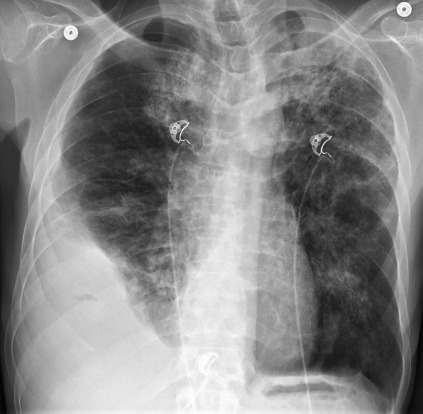

The most likely diagnosis in the case illustrated in Fig. 4.1 is:

• a.

Necrotizing pneumonia with empyema.

• b.

Tuberculosis.

• c.

Lung cancer.

• d.

Mesothelioma.

• e.

Metastases.

Fig. 4.1

Pleural effusions may produce blunting of a costophrenic angle (see Fig 4.1 ), apparent elevation of the diaphragm (see Fig 4.2, A ), peripheral homogeneous opacity with a line that parallels the lateral chest wall ( Fig 4.3 ), opacity in interlobar fissures ( Fig 4.4, A-D ), 465 or complete opacification of an entire hemithorax, with a shift of the mediastinum ( Fig 4.5 ). Detection and confirmation are often the first steps in the evaluation of a suspected pleural effusion. Small effusions with opacification of the costophrenic angle may be confirmed by a lateral decubitus examination, with the side of the suspected effusion down. The decubitus examination may show a change in position of the opacity and confirm free-flowing effusion. No change in the opacity may be the result of loculated effusion, pleural scarring, or possibly a pleural mass. Prior chest radiographs indicating that the blunting is a new finding also provide a good indicator of pleural effusion. Loculated effusions are difficult to confirm with chest radiograph, but ultrasound, computed tomography (CT), and even magnetic resonance imaging (MRI) may be used to verify a localized collection of pleural fluid. The differential diagnosis of pleural effusion entails consideration of a long list of entities ( Chart 4.1 ), 465 but the radiologist should not be discouraged. 478 Pleural effusion is sometimes associated with additional radiologic findings that may be very specific, but clinical and laboratory correlation are almost always required to make a specific diagnosis.